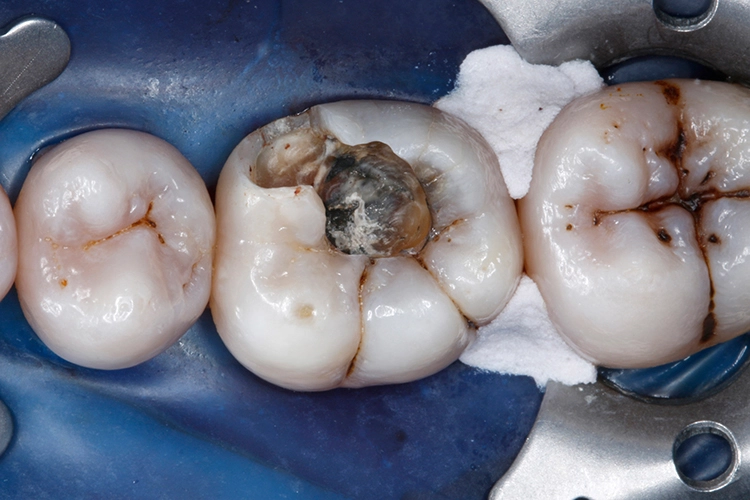

Ein 38-jähriger Patient erschien in unserer Sprechstunde mit einem frakturierten mesiolingualen Höcker neben einer okklusalen Amalgamfüllung am unteren rechten 1. Molaren (Zahn 46). Der Vorfall hatte sich bereits vor einer Woche ereignet, der Zahn war noch am selben Tag im zahnärztlichen Notdienst provisorisch mit einer Glasionomerzementfüllung versorgt worden (Abb. 1). Der Defekt erstreckte sich bis auf Höhe der marginalen Gingiva (Abb. 2).

Nachfolgend wurde mit dem nächsten Inkrement VisCalor das restliche Kavitätenvolumen (maximale Schichtstärke: 2 mm) komplett aufgefüllt (Abb. 21). VisCalor kühlt innerhalb weniger Momente nach Kontakt mit dem Zahn durch Wärmeleitung (Konduktion) schnell wieder auf Mundhöhlentemperatur ab und nimmt somit wieder eine hochviskose Konsistenz an (Abb. 22), die eine Modellation der Kauflächenanatomie erleichtert.